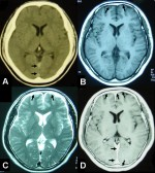

A 33-year-old male complaining of recurrent left hemiparesis for 22 days was admitted into our hospital. The clinical characteristics and CT, MRI, and pathological data were investigated carefully. IHCP was diagnosed and pulse corticosteroid therapy was used to treat this case. Headache, neck pain and recurrent episodes of weakness and numbness in the left limbs were the main clinical manifestations. CT and MRI revealed thickening of the dura along the falx and tentorium. Meningeal biopsy showed diffused thickening of the dura, consisting of collagen in concentric form with inflammatory cell infiltrating and fibrinoid necrosis, confirmed to be dura mater by histopathological examination. Treatment with an antiplatelet drug, low molecular heparin and herbs did not prevent the attacks. Pulse corticosteroid therapy was used and good efficiency was achieved.